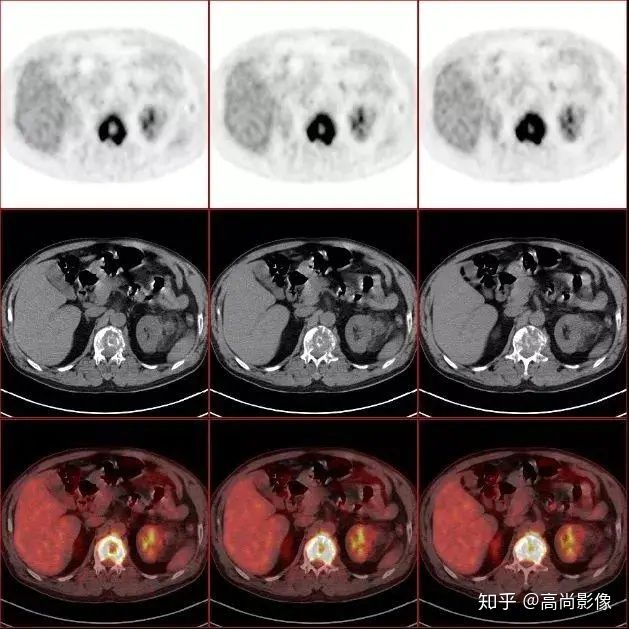

(胸椎骨轉(zhuǎn)移合并病理性骨折)

(右側(cè)髖臼骨轉(zhuǎn)移)

(右肺癌全身多發(fā)轉(zhuǎn)移)

(右肺上葉中央型肺癌)

方大爺?shù)腜ET/CT結(jié)果強烈提示肺癌伴全身多發(fā)轉(zhuǎn)移,已經(jīng)失去手術(shù)機(jī)會,但仍有繼續(xù)化療的機(jī)會。

與方大爺有類似病情的一位患者,化療前后的PET/CT影像顯示,腫瘤得到了很好的控制。

肺癌化療前評估的MIP圖

(最大密度投影圖)

肺癌化療后評估的MIP圖

由此可見,惡性腫瘤化療前后的全身PET/CT評估有多重要,尤其對于惡性腫瘤患者來說,時間就是生命,早一天完善診斷,早一天得到正確的治療,預(yù)后就會更佳。